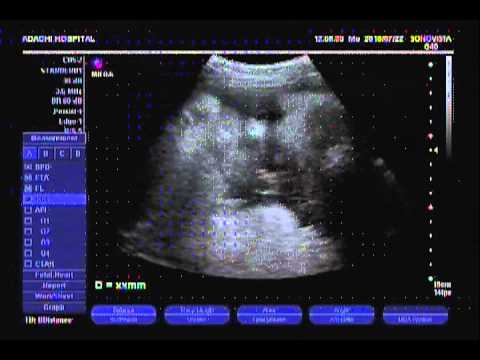

妊婦9ヶ月健診 34週4日 2013 07 22 エコー 逆子が直ってました Youtube

エコー